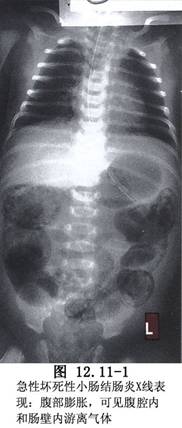

急性壞死性小腸結腸炎泛指小腸或結腸的急性瀰漫性或侷限性炎症。病變可沿腸管的長度漫延,也可穿過黏膜和肌層而發生穿孔。新生兒期間發病,尤多見於未成熟兒體重在1500g左右者。近年發病有增加的趨勢,約佔新生兒外科病兒的3%~15%(圖12.11-1)。